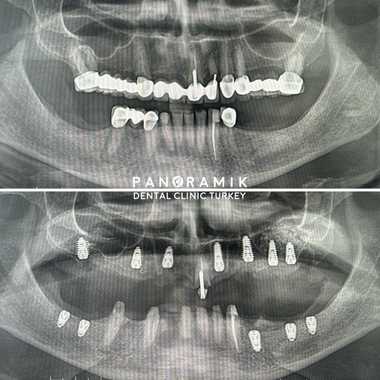

Image-1: Sinus lifting